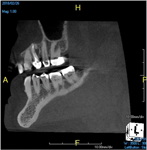

The idea that a dentist may be incorrect in his or her diagnosis is distasteful, but a reality that this profession wrestles with on a daily basis. An image comparison can help to clarify this thought. The first image is a 2D radiograph of tooth No. 19 that includes the buccal cortical plate the lingual cortical plate and approximately 10 mm of trabecular bone compressed into a single image (Figure 1). Because the full width and volume of the tooth is included in the image, any existing pathoses could be masked or hidden in a fog of digital information. A CBCT scan of the same tooth provides more detail because it can present a slice (0.1 mm) of information from the center of the area in question (Figure 2). All of the extraneous information is eliminated, and the clinician and the patient have a more precise picture to evaluate. Furthermore, a periapical radiograph can be distorted by the angle of the cone to the sensor, whereas a CBCT scan has no distortion and is accurate in all views. With a CBCT scan, the clinician is able to state with certainty that a condition exists, and the patient is able to more clearly understand what his or her condition is when considering the available choices for treatment.

(1. ) Two-dimensional periapical radiograph of tooth No. 19 compared with a CBCT scan slice (0.1 mm) of the same tooth, which reveals a well-defined lesion that a patient can more easily understand.

Figure 1

(2.) Two-dimensional periapical radiograph of tooth No. 19 compared with a CBCT scan slice (0.1 mm) of the same tooth, which reveals a well-defined lesion that a patient can more easily understand.

Figure 2